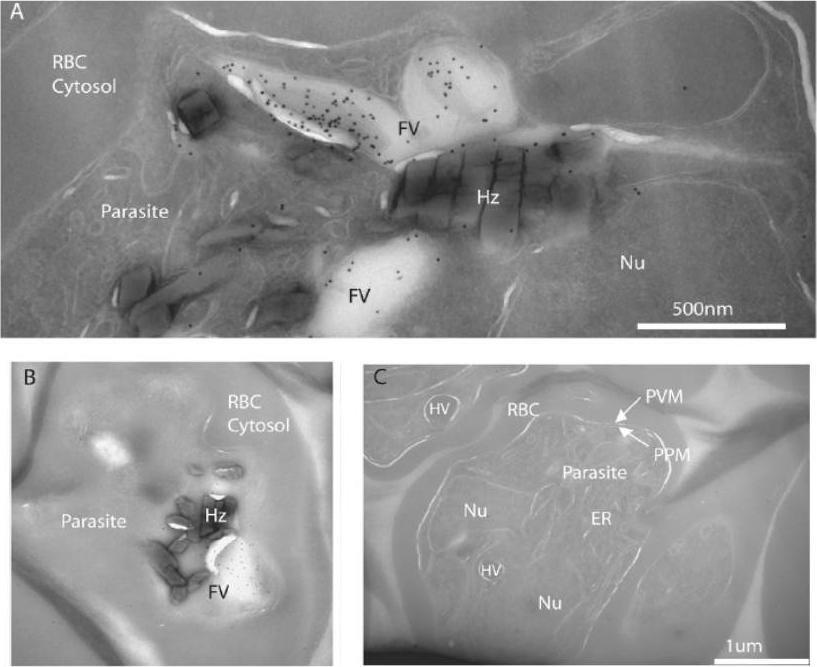

FCP localizes to the lumen of the FV. A, cryo-immunoelectron micrograph showing a close-up of a folded FV with immunogold-stained FCP in the lumen of the parasite FV in a late trophozoite. Various structures are indicated as host red blood cell cytosol (RBC Cytosol), parasite body (parasite), parasite nucleus (Nu), FV, and hemozoin (Hz). B shows a more complete parasite with a cross-section through the FV indicating a lack of immunogold staining outside the FV. C, three parasites from a different region of the same ultrathin section that was immunogold-stained for anti-FCP in A and B. Note the lack of concentrated gold particles on all visible parasite structures including ER, parasite plasma membrane (PPM), parasitophorous vacuolar membrane (PVM), and hemoglobin containing vesicles (HV). McIntosh MT, Vaid A, Hosgood HD, Vijay J, Bhattacharya A, Sahani MH, Baevova P, Joiner KA, Sharma P. Traffic to the malaria parasite food vacuole: a novel pathway involving a phosphatidylinositol 3-phosphate-binding protein. J Biol Chem. 2007 282:11499-508.